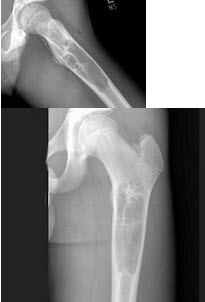

E.老年人

女,31岁,左侧髋部疼痛1月余,有压痛,压之有捏乒乓球感,结合影像学检查,最可能的诊断是()

A.骨囊肿

B.骨巨细胞瘤

C.动脉瘤样骨囊肿

D.成软骨细胞瘤

E.骨结核